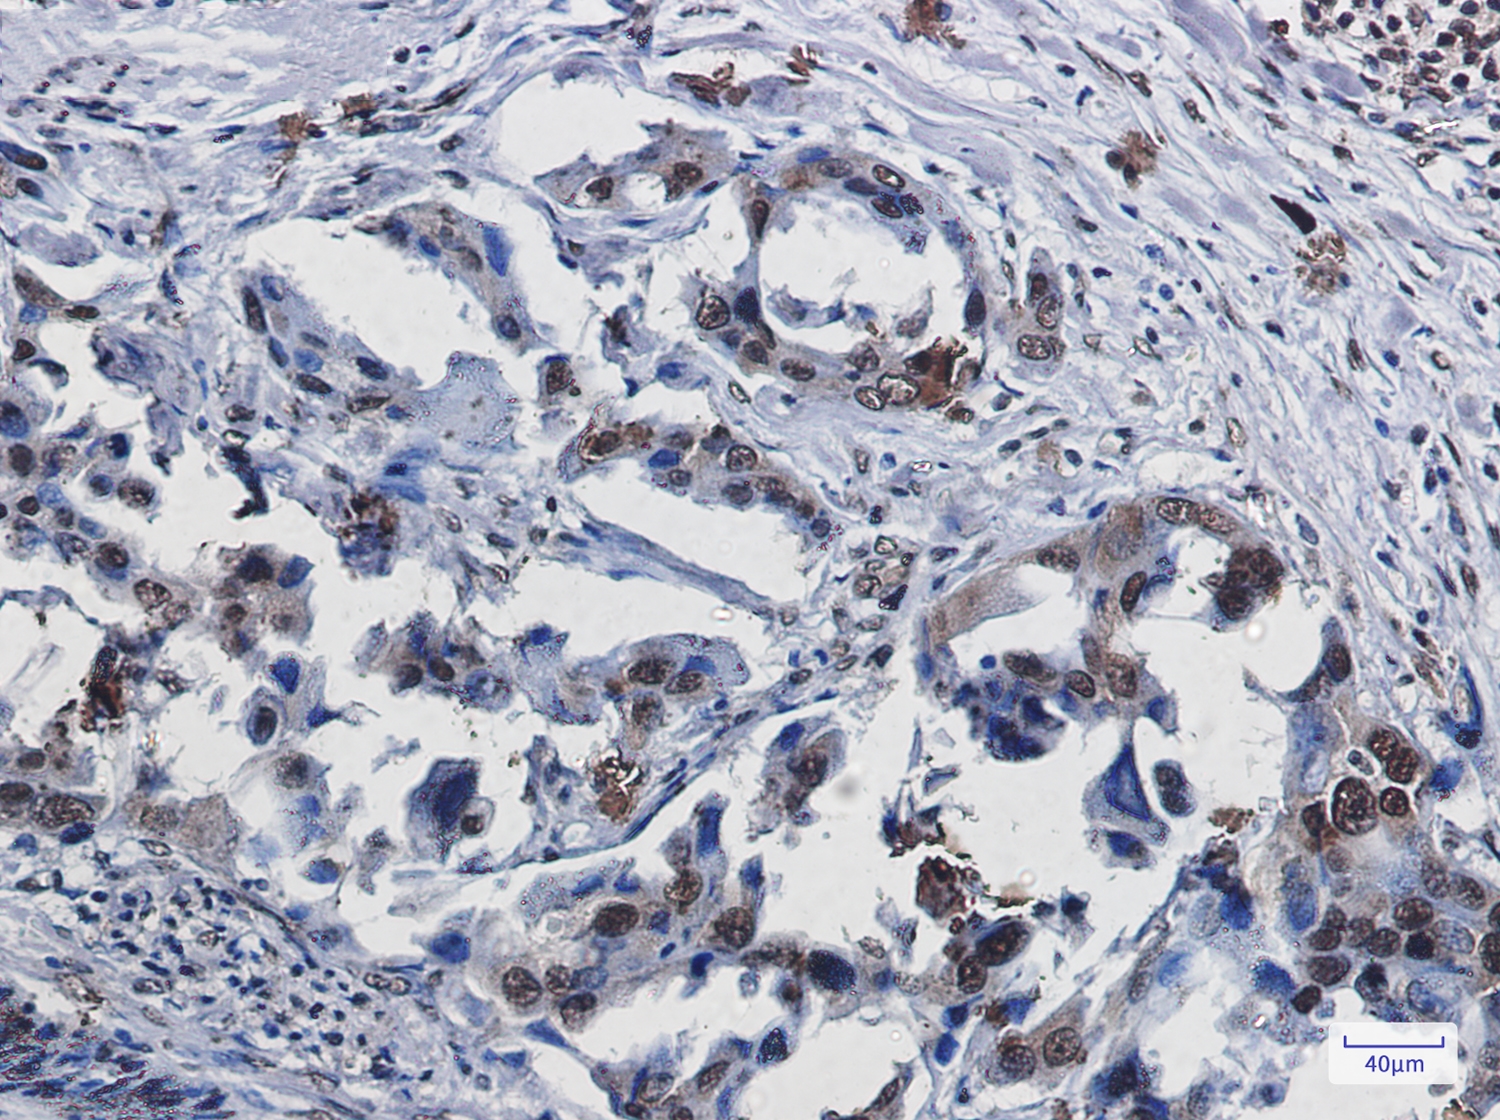

文献和实验:使用 Anti-phospho-Akt (Ser473) Rabbit mAb 对石蜡包埋的人乳腺癌组织进行免疫组织化学分析。(图 A)使用免疫组化试剂盒M&R HRP/DAB Detection IHC Kit,抗体 1:100 稀释;(图 B) 采用普通免疫组化试剂盒,抗体 1:25 稀释。 图 6 免疫组化实验检测 Erk1/2 表达 注:使用 Anti-Erk1/2 Mouse mAb与p44/42 MAPK (Erk1/2)Rabbit mAb 对正常小鼠心脏组织进行免疫